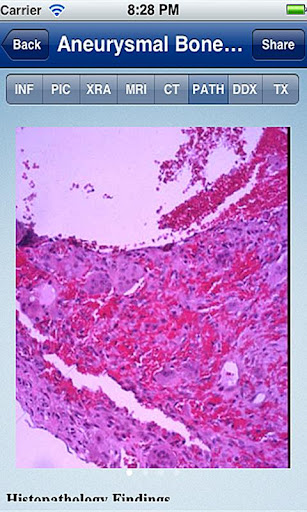

Each Tumorpedia app contains information on 20 to 50 different tumors, covering the etiology, pathogenesis, clinical presentation, and examination findings, as well as the xray, MRI, and CT scan appearance of the tumor. The diagnostic features of each tumor are illustrated with hundreds of images from actual case examples. In addition, the microscopic pathology findings are described and illustrated. The app provides treatment options, outcomes information, and prognosis for each tumor.